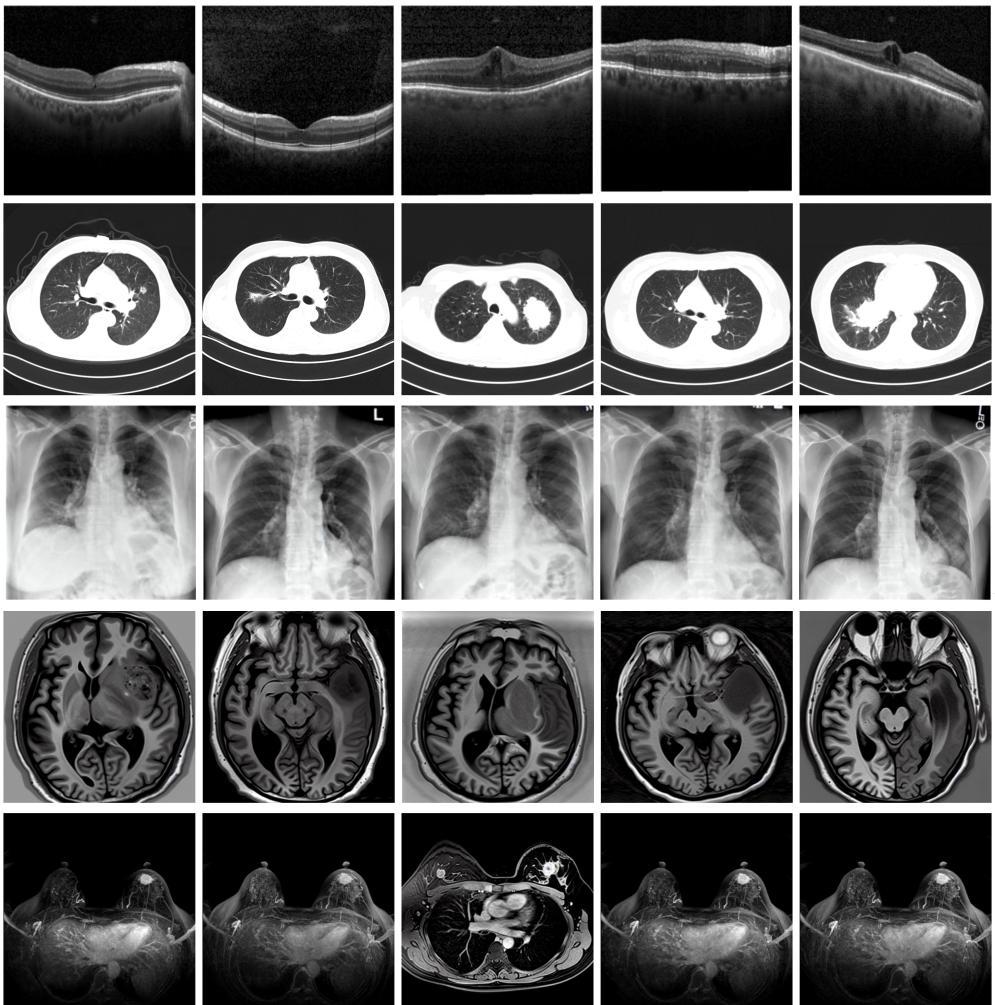

圖為由MINIM生成的高質(zhì)量醫(yī)學合成圖像(受訪者供圖)

“目前公開的醫(yī)學影像數(shù)據(jù)非常有限,我們建立的生成式模型有望解決訓練數(shù)據(jù)不夠的問題?!北本┐髮W未來技術(shù)學院助理研究員王勁卓說,研究團隊利用多種器官在CT、X光、磁共振等不同成像方式下的高質(zhì)量影像文本配對數(shù)據(jù)進行訓練,最終生成海量的醫(yī)學合成影像,其在圖像特征、細節(jié)呈現(xiàn)等多方面都與真實醫(yī)學圖像高度一致。

實驗結(jié)果顯示,MINIM生成的合成數(shù)據(jù)在醫(yī)生主觀評測指標和多項客觀檢驗標準方面達國際領(lǐng)先水平,在臨床應用中具有重要參考價值。在真實數(shù)據(jù)基礎(chǔ)上,使用20倍合成數(shù)據(jù)在眼科、胸科、腦科和乳腺科的多個醫(yī)學任務準確率平均可提升12%至17%。